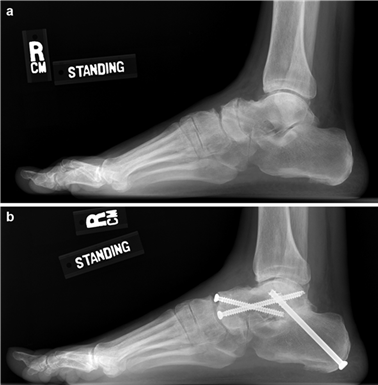

Weight-bearing anteroposterior (AP), lateral, and sesamoid axial radiographs are mandatory. On the AP view, the surgeon measures the Hallux Valgus Angle (HVA, normal < 15°), the Intermetatarsal Angle (IMA, normal < 9°), and the Distal Metatarsal Articular Angle (DMAA). The lateral view is scrutinized for Meary's angle (talo-first metatarsal angle) to identify midfoot collapse, as well as the presence of dorsal osteophytes indicative of hallux rigidus. The sesamoid axial view is critical for assessing the degree of sesamoid subluxation and the integrity of the crista.

Image

The Lapidus Arthrodesis (First TMT Fusion)

For severe deformities or hypermobility, the Lapidus procedure provides robust stabilization of the medial column. A dorsal or medial incision is utilized over the first TMT joint. The extensor hallucis longus (EHL) is retracted dorsally, and the tibialis anterior tendon is identified and protected at its insertion on the medial cuneiform and first metatarsal base. The TMT joint capsule is incised, and the joint is thoroughly debrided of all articular cartilage using a combination of osteotomes, curettes, and a high-speed burr.

To achieve multiplanar correction, the surgeon must address the sagittal, coronal, and transverse planes. The first metatarsal is plantarflexed to restore the longitudinal arch, rotated out of pronation to realign the sesamoids, and translated laterally to close the IMA. Subchondral drilling or feathering is performed to optimize the biological environment for fusion. Fixation is traditionally achieved with two or three crossed solid or cannulated screws (typically 3.5mm or 4.0mm). Recently, plantar or medial locking plates have gained immense popularity due to their superior biomechanical construct, allowing for earlier weight-bearing. Bone graft or orthobiologics may be packed into the arthrodesis site to stimulate osteogenesis.